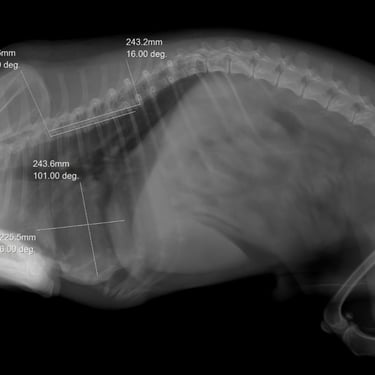

Radiología veterinaria

Ofrecemos servicios de radiología móvil para pequeños animales y equinos, orientados a apoyar el diagnóstico veterinario mediante estudios radiográficos realizados en el lugar o campo. Este servicio está pensado para clínicas veterinarias y contextos rurales, reduciendo el estrés del traslado y facilitando la evaluación diagnóstica. Contamos con formación y certificaciones en radiología veterinaria, aplicando protocolos adecuados y normas de seguridad radiológica, y trabajando en conjunto con el veterinario actuante para aportar imágenes confiables que acompañen la toma de decisiones clínicas.